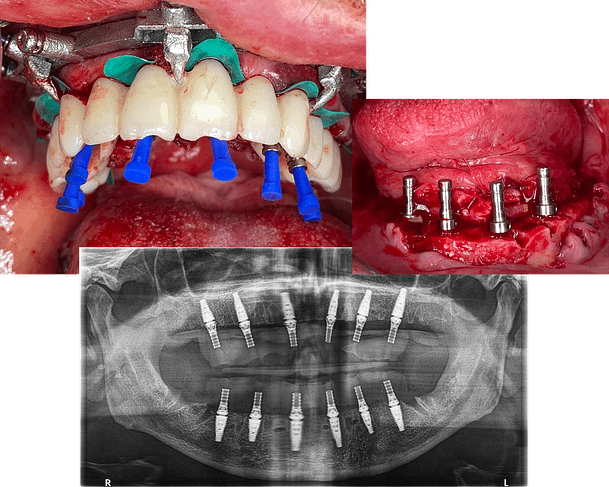

After